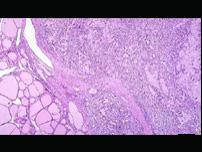

问题 不符合髓样癌特征的是()

选项 A.来源于腺上皮 B.癌巢呈实体性,无腺腔形成 C.癌细胞多 D.可见淋巴细胞浸润 E.纤维间质丰富

答案 E